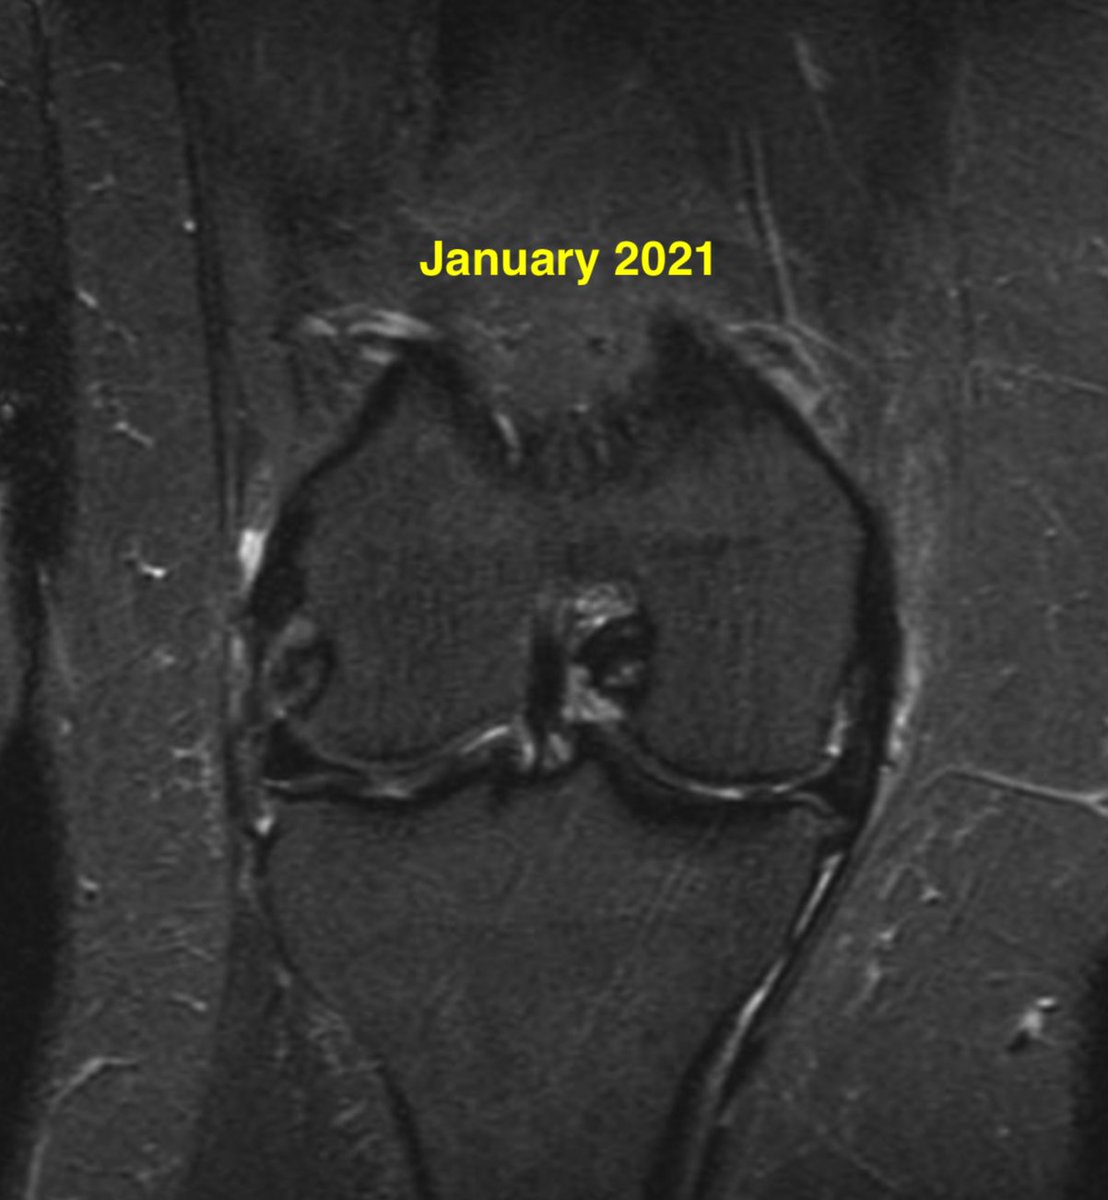

Meniscus root tears are important to recognize and address. Unfortunately, the natural history of a medial meniscus root tear can be seen in this patient when left untreated, with rapid progression of medial arthritis. #savethemeniscus #orthotwitter

Daniel Liechti, MD tweet mediaDaniel Liechti, MD tweet mediaDaniel Liechti, MD tweet mediaDaniel Liechti, MD tweet media